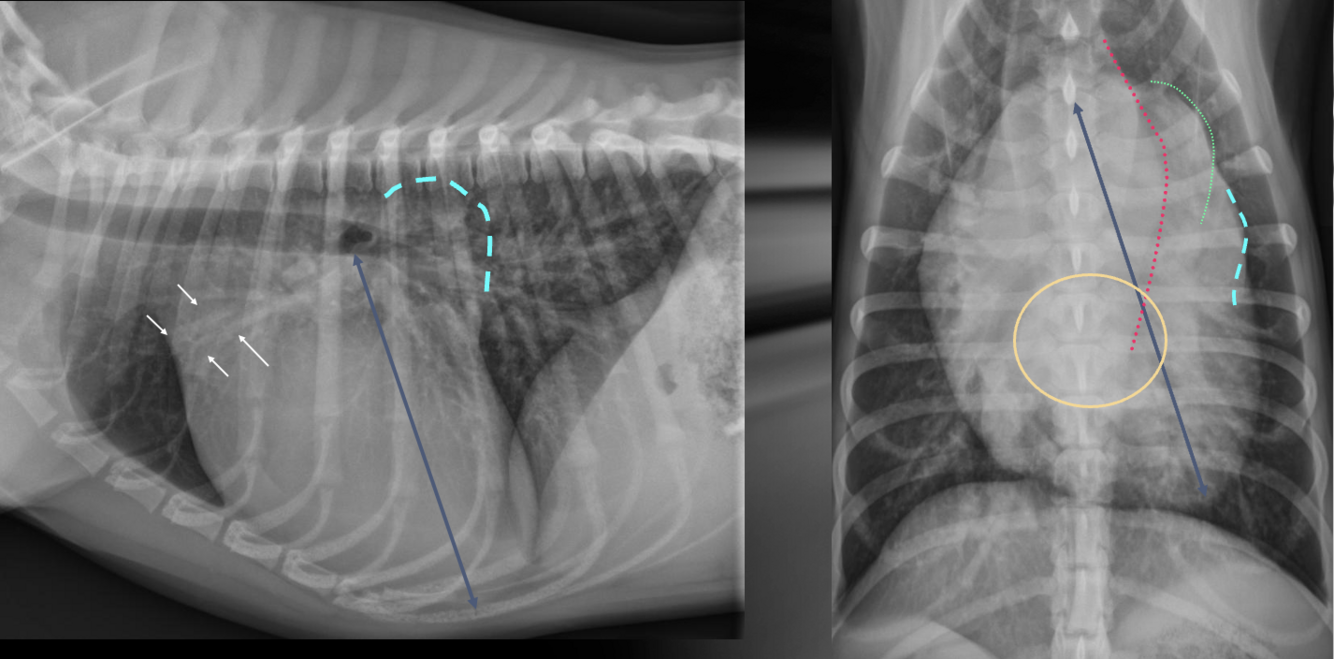

Q

What is shown in these images?

A

(sub)aortic stenosis

-left heart enlargement

-elongation of cardiac silhouette

-increased prominence of aortic arch